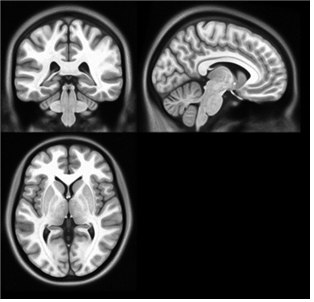

서울의대 김기웅 교수(분당서울대병원 정신건강의학과)가 뇌질환이 없는 60세 이상 정상 노인 96명의 MRI를 분석해 '한국 노인의 표준 뇌'를 개발했다고 21일 발표했다.

이러한 문제를 해결하려고 김 교수는 60세 이상의 우리나라 노인 96명의 MRI 영상으로 '한국 노인'의 표준뇌를 개발하게 된 것이다. 한국노인의 뇌 모양을 대표하는 표준뇌인 만큼, 뇌의 형태에 영향을 줄 수 있는 다양한 질환들을 포괄적이고 정밀한 임상 검사를 통해 철저히 배제하는 등 엄격한 대상 선정 과정을 거쳤다.

분석 결과 예상대로 서양인의 표준 뇌와 한국 노인의 표준 뇌는 크게 달랐다. 좌우 폭의 경우 한국 노인이 약간 넓고 앞뒤 길이와 상하 높이는 서양인이 큰 차이로 길거나 높았다.

이 차이를 바탕으로 한국인의 뇌 영상을 분석할 때 서양인의 표준뇌를 사용하면 발생할 수 있는 오류의 정도를 측정한 결과, 많은 왜곡이 발생할 수 있는 것으로 나타났다.